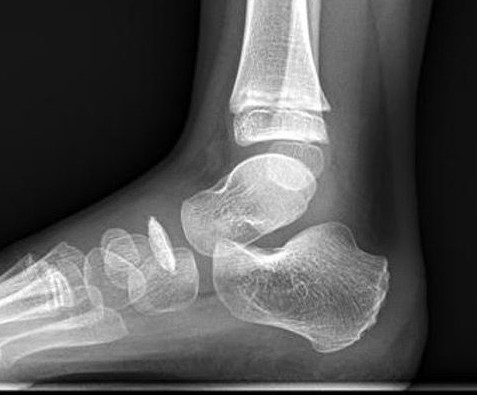

X-ray

Flattening / sclerosis / fragmentation of navicular